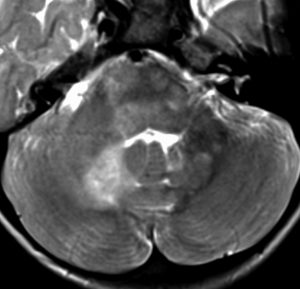

脳幹部のUBOです,大きくなると脳幹部神経膠腫に間違えられることがあります

脳幹部グリオーマと間違えそうなもの

3歳の時に,MRIで脳幹部から小脳のグリオーマを疑われて受診しました。橋が腫れて右小脳にもグリオーマのような白い影があります。でもこれは,NF-1のUBOの大きなものです。びまん性正中グリオーマと誤診されて放射線治療を受けてしまった子供もみたことがあります。治療しなくても縮小していくので,何もしないで経過観察します。右側のMRIは13年後のものです。ほとんど消失しています。